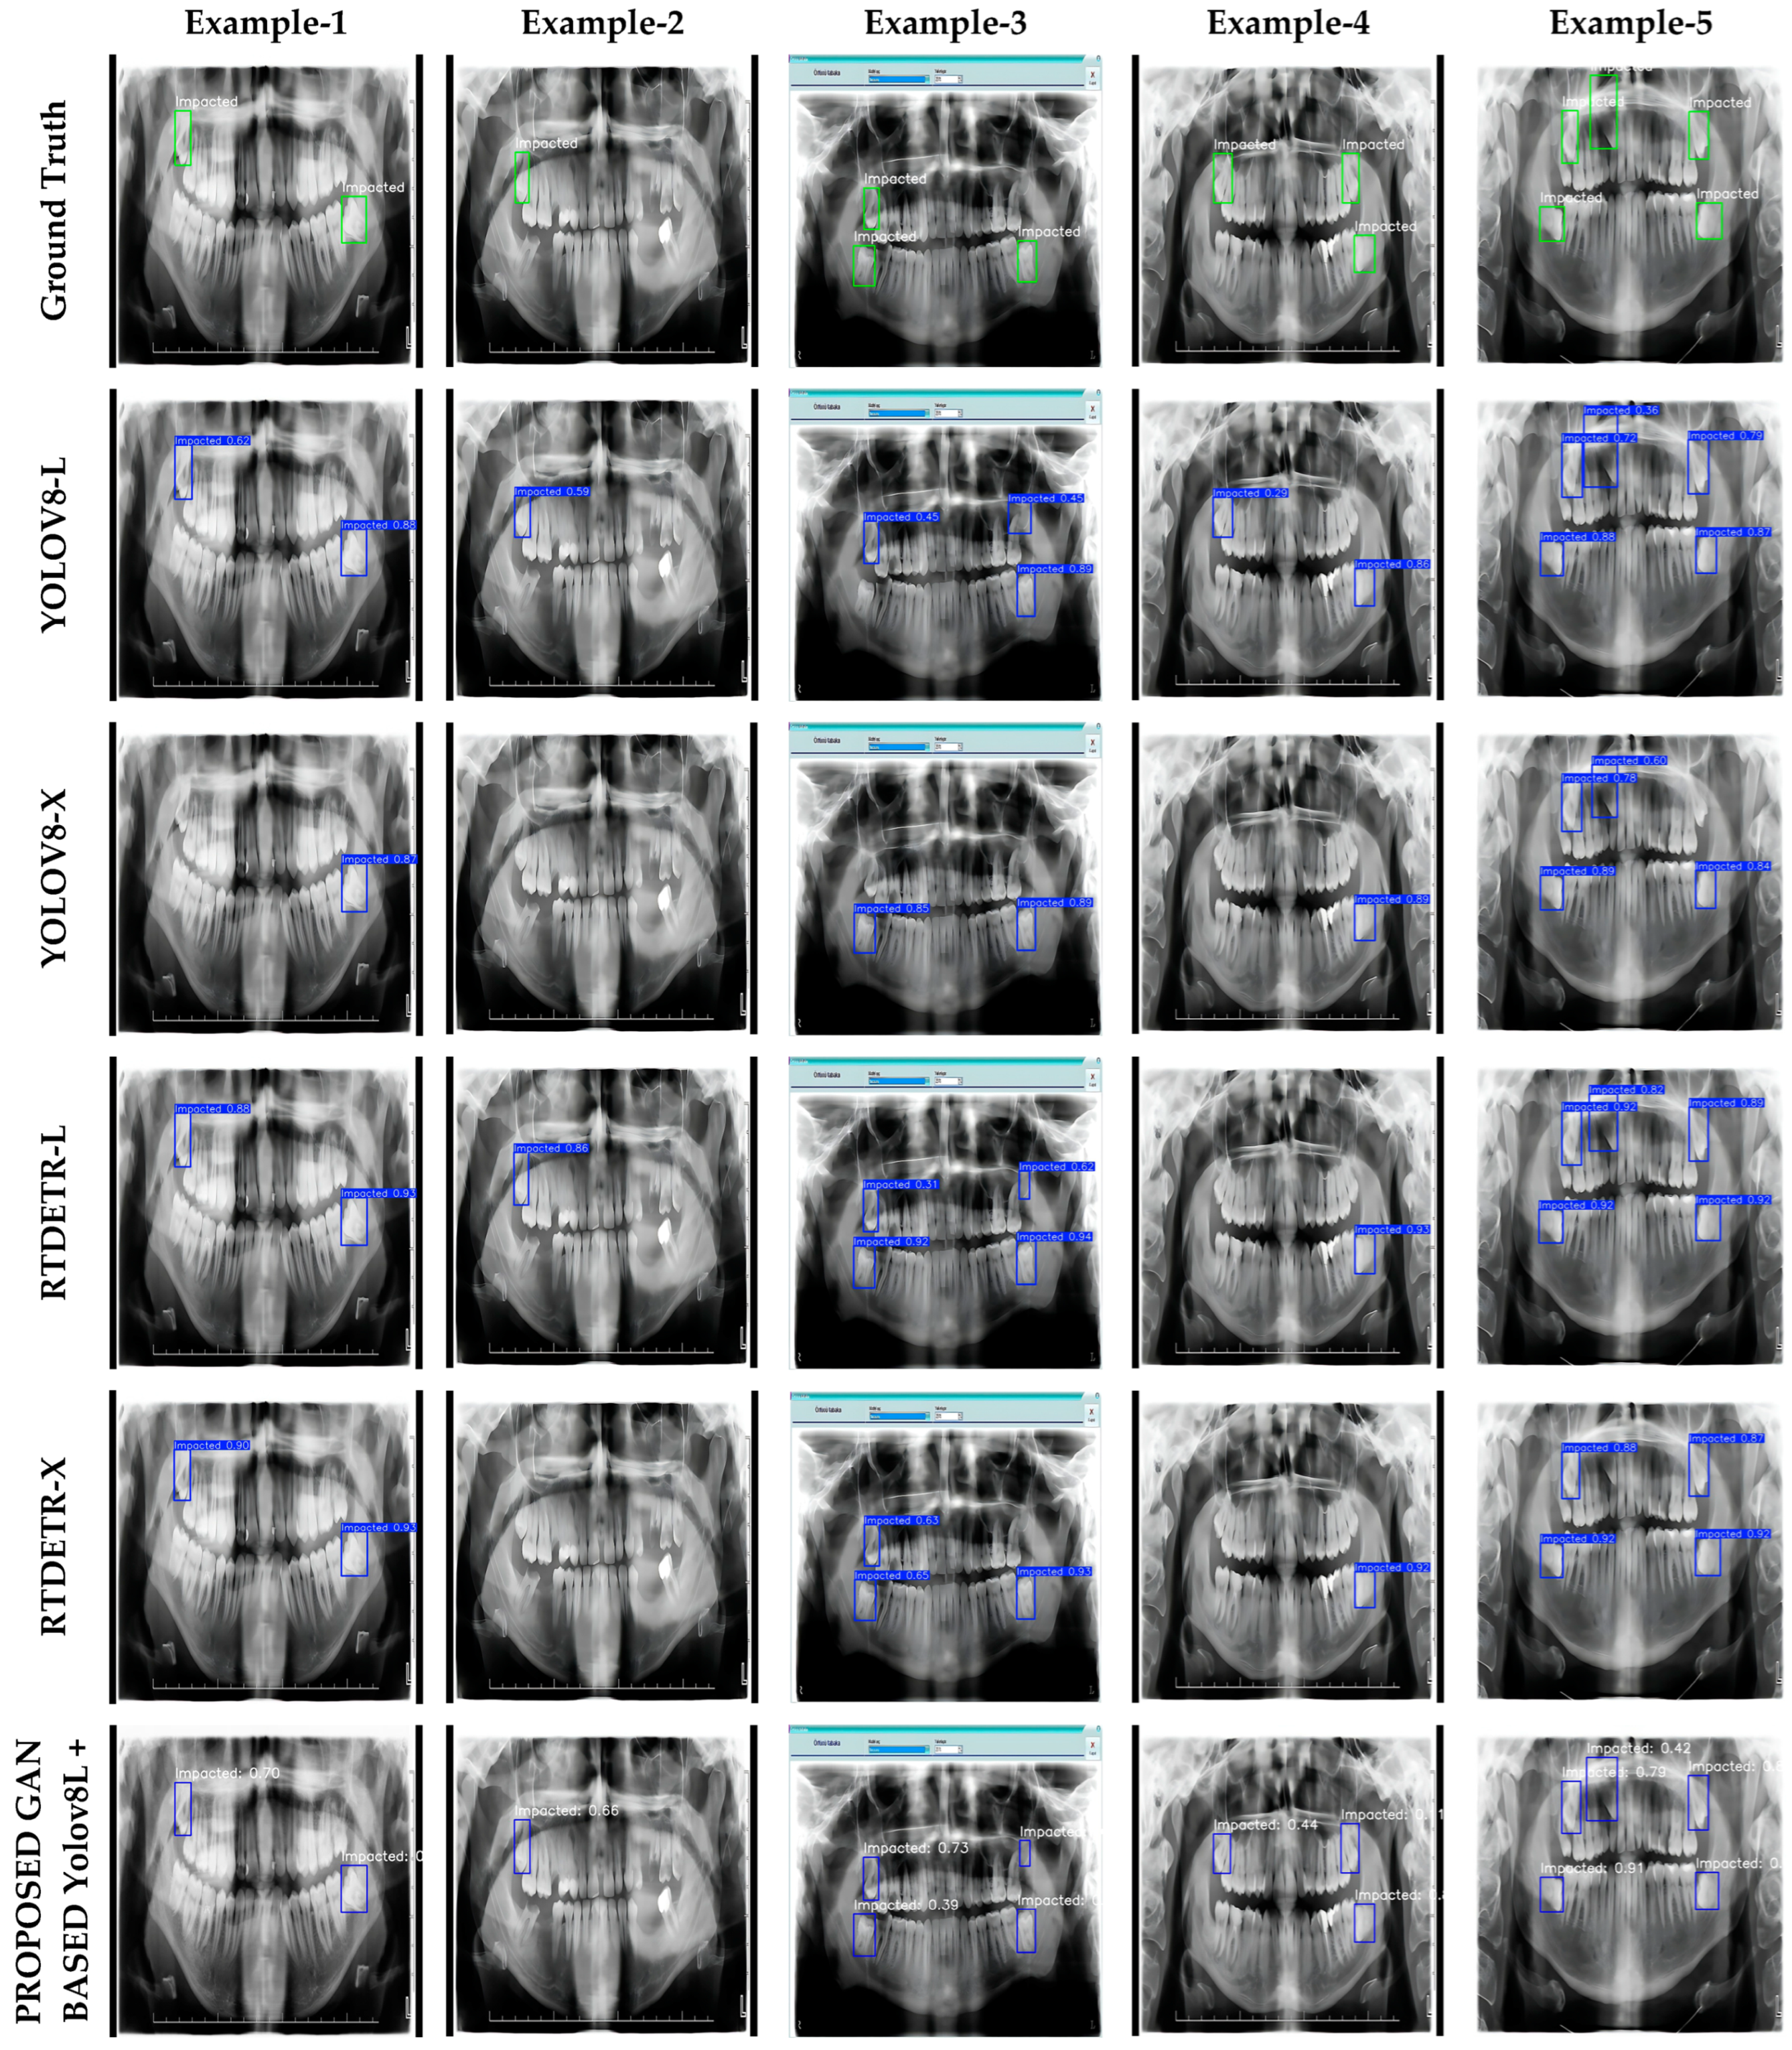

3.1. Individual Results

- The YOLOv8L model achieved the highest F1 values (94.6% and 94.5%) with both normal and GAN-based super-resolution images. It was also observed that mAP@0.5 (96.5%) improved with GAN-based images. These results show that YOLOv8L performs well with both image types. On the other hand, the YOLOv8X model performed similarly on normal and GAN-based images (88.8% mAP@0.5 and 93.7% F1). This suggests that the effect of GAN-based super-resolution on this model is limited.

- RT-DETR-L achieved the highest IoU score of 95.2% mAP@0.5 for normal images. However, this value decreased slightly to 94.7% for GAN-based images. In contrast, the GAN enhancement resulted in a significant increase in the F1 score (from 88.2% to 92.3%). On the other hand, RT-DETR-X showed a balanced performance on both normal and GAN-based images. However, there was a slight decrease in mAP@0.5 (92.3%) and F1 (91.7%) after GAN enhancement.

3.4. Visualization